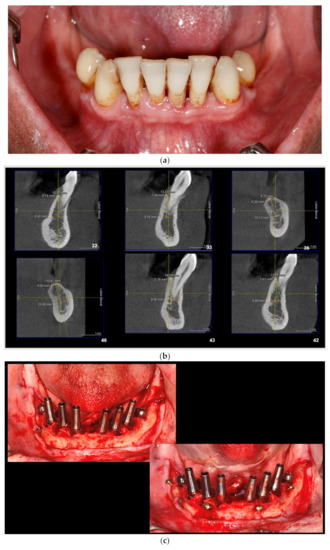

Intraoral view aspects and CBCT images of the implant sites, from a patient included in the test group, are presented in Figure 1a–o (reconstruction of the implant sites by S-GBR technique with porcine-derived xenograft material).

Figure 1.

(a) A.C., aged 65. Preoperatory intraoral view. (b) Preoperative CBCT images and alveolar bone parameters measured with Sidexis XG/ DVT (Densply/Sirona) software. (c) Intraoral view after the insertion of osteosynthesis screws and implants. (d) Intraoral view after the mandibular alveolar reconstruction with S-GBR technique and porcine xenograft. (e) Postoperative intraoral view after wound suture and temporary loading. (f) Alveolar bone width values measured at baseline (left) and at 6 months follow-up with Sidexis XG/ DVT software (Densply/Sirona). (g) Alveolar bone width values measured at baseline (left) and at 6 months follow-up with Sidexis XG/ DVT software (Densply/Sirona). (h) Alveolar bone width values measured at baseline (left) and at 6 months follow-up with Sidexis XG/ DVT software (Densply/Sirona). (i) Alveolar bone width values measured at baseline (left) and at 6 months follow-up with Sidexis XG/DVT software (Densply/Sirona). (j) Alveolar bone osteodensity values measured at baseline (left) and at 6 months follow-up (right) (implant site 4.1). (k) Alveolar bone osteodensity values measured at baseline (left) and at 6 months follow-up (right) (implant site 4.5). (l) Alveolar bone osteodensity values measured at baseline (left) and at 6 months follow-up (right) (implant site 3.2). (m) Alveolar bone osteodensity values measured at baseline (left) and at 6 months follow-up (right) (implant site 3.5). (n) Preloading intraoral view. (o) Postloading intraoral view.